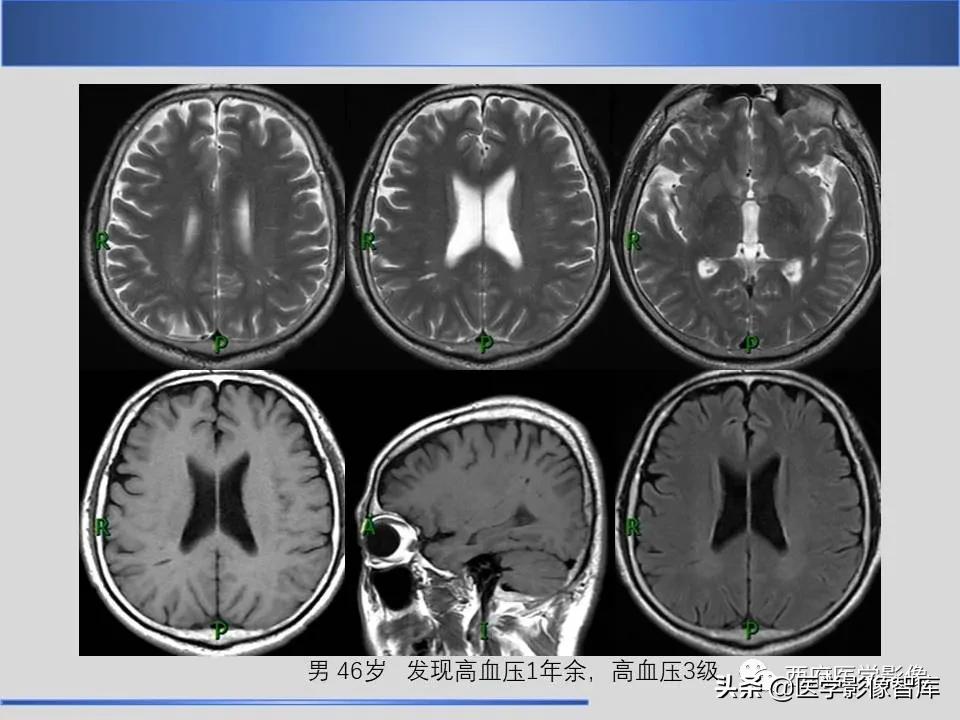

vr间隙是什么意思 (vr间隙诊断意义)

作者:张育苗(宝鸡市中心医院医学影像科)

来源: 西府医学影像